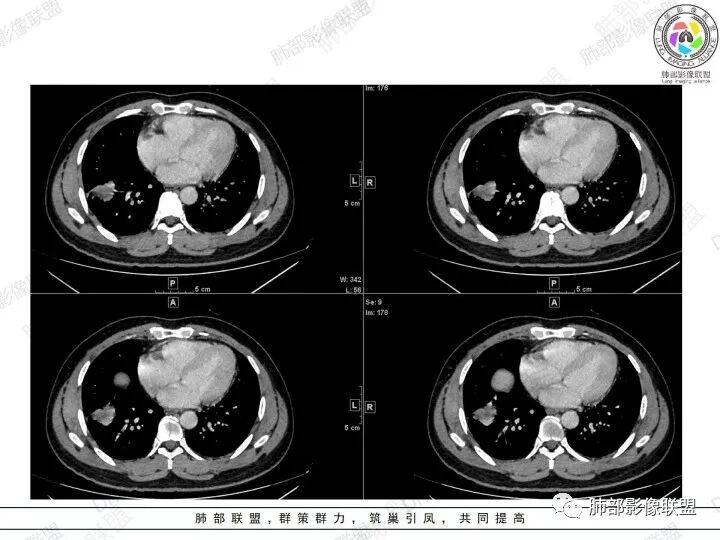

2、胸部CT右肺下叶胸膜下肿块性病变,边缘可见分叶毛刺、边缘膨隆,似有指状凸起,邻近胸膜稍牵拉凹陷,叶间裂以为不明显,提示收缩力较弱。近端支气管进入后截断,病灶内密度尚均匀,增强后可见轻度强化,未见空洞或钙化,并可见血管影进入。右侧肺门及纵隔内可见肿大淋巴结影。无胸腔积液。

3、综合患者临床症状及影像表现,需要考虑肿瘤性病变和非肿瘤性病变,肿瘤性病变需要考虑普通浸润性腺癌或结节型粘液腺癌、淋巴瘤、淋巴上皮瘤样癌、小细胞肺癌等,非肿瘤性病变主要考虑肺脑同病中的隐球菌。①普通浸润性腺癌,以肺外周多年、混合磨玻璃或实性结节/肿块,多见分叶、毛刺、胸膜凹陷、血管集束等征象,本例收缩力较弱、且强化偏轻,不够典型。②粘液腺癌,腺癌的特殊类型。多位于胸膜下(90%位于胸膜下,70%位于下叶胸膜下),边缘清或不清的GGO:提示粘液外渗,少数为纯GGO,缺乏中心纤维化区:毛刺、胸膜凹陷征少,很少胸膜侵犯,淋巴结转移少见,增强后无强化或低强化,本例病灶位于胸膜下,强化轻,收缩力弱,结节期粘液腺癌确实可以符合。③小细胞肺癌,吸烟男性多见,典型征象包括娘小崽大、腊肠样凸起、冰冻纵膈等,本例胸膜下病变大、但肺门淋巴结肿大程度较轻,不符合常见小细胞癌生物学行为,但有可疑指状凸起,小细胞肺癌不能完全除外。④淋巴上皮瘤样癌,少见的恶性肿瘤,患病年龄较轻,肿瘤多位于胸膜下,边缘多光滑,病灶周围可见磨玻璃,毛刺及分叶、胸膜凹陷少见,近端支气管可截断,增强多为中度-明显强化,本例除了强化程度偏轻外,影像表现基本可符合。⑤淋巴瘤,原发肺内淋巴瘤较少见,病灶多位于支气管血管束周围或胸膜下,密度多较均匀,边缘可膨隆也可平直收缩,可见支气管充气征、血管造影征等,强化多为轻中度,本例肺内结节血管穿行自然,局部有血管漂浮,长轴与支气管走行基本一致,肺门淋巴结肿大,不能排除。⑥隐球菌,影像表现可分为孤立结节型、大片实变型、多发结节或实变型、弥漫型。病变多位于胸膜下,边缘平直为主、可伴晕征,可见支气管穿行、部分可见支气管截断,密度多较均匀,部分可伴空洞,增强多为轻中度强化、延迟强化。本例病变位于胸膜下,收缩力弱,强化程度轻,但没有呼吸道症状,病变近端支气管截断,肺门淋巴结大,这些征象都难以用隐球菌解释,基本排除。

结节型粘液腺癌的影像诊断:

1.位于胸膜下(90%位于胸膜下,70%位于下叶胸膜下)

2.边缘清或不清的GGO:提示粘液外渗,少数为纯GGO

3.缺乏中心纤维化区:毛刺、胸膜凹陷征少,很少胸膜侵犯率

4.淋巴结转移少见

5.增强后无强化或低强化

6.典型征象:圆圈征、草帽征、树上蘑菇征、GGO样卫星灶